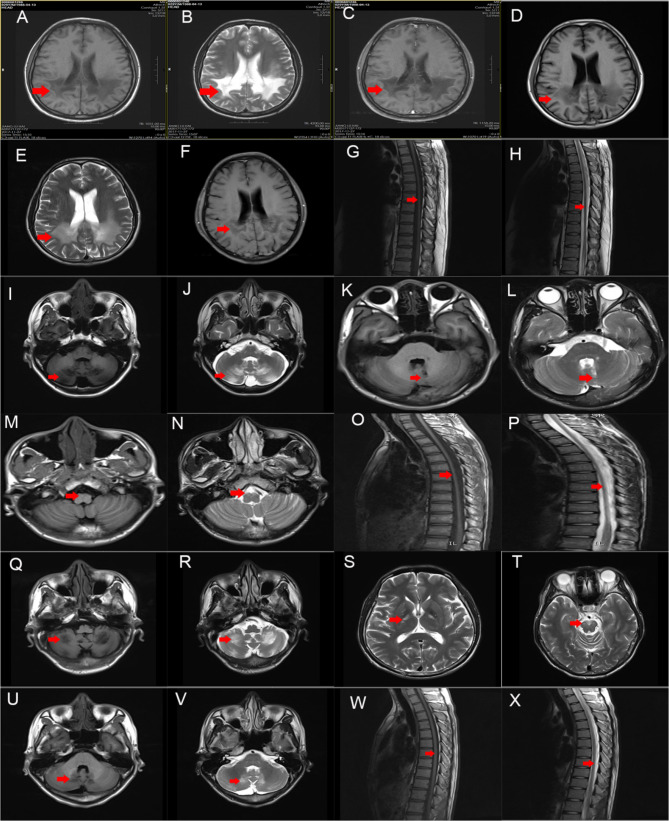

Case presentation: Seven adult-onset ALD patients of Chinese descent were enrolled in the study. Detailed clinical characteristics, laboratory results, imaging findings and genetic testing of the patients were collected and analyzed. All seven patients diagnosed with adult-onset ALD were male, including two with adult cerebral ALD (ACALD), one with adrenomyeloneuropathy (AMN), and four presenting with the spinocerebellar variant. The primary clinical manifestations of the two ACALD patients were progressive cognitive dysfunction and psychiatric symptoms. The AMN patient showed chronic progressive spastic paraplegia and displayed non-specific thoracic spinal cord atrophy on MRI. Symptoms observed in the four patients with spinocerebellar variant included cerebellar ataxia, dysarthria, spastic paraplegia, peripheral neuropathy, sphincter dysfunction, and alopecia. These four patients all demonstrated symmetrical white matter hyperintensity (WMH) in the cerebellum on brain magnetic resonance imaging (MRI). Additionally, two of these patients exhibited abnormal MRI signals in the pyramidal tract. All the patients had an elevation of VLCFAs, which is diagnostic for ALD. One patient exhibited elevated adrenocorticotropic hormone (ACTH) and decreased cortisol levels, while six patients displayed slightly elevated ACTH levels and normal cortisol levels without any clinical signs of adrenal insufficiency. Genetic testing identified four known ABCD1 pathogenic variants as well as two novel pathogenic variants.

Conclusions: Progressive cognitive impairment and behavioral abnormalities are common clinical manifestations of ACALD. AMN and the spinocerebellar variant are prevalent phenotypes of adult-onset ALD. Patients with adult-onset ALD may present with isolated WMH in the cerebellum on brain MRI. Routine screening for ALD should be conducted in male patients diagnosed with Addison's disease. Subclinical adrenal cortex insufficiency is a common finding in adult-onset ALD. Elevated levels of VLCFA function as a reliable clinical biomarker for ALD. The identification of novel pathogenic variants in ABCD1 broadens the genetic spectrum of ALD.